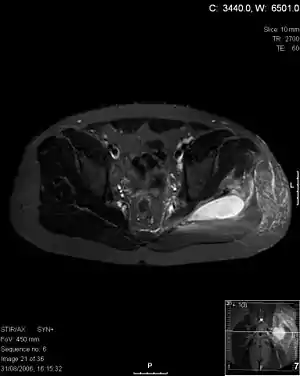

| Transverse T2 magnetic resonance imaging section through the hip region showing abscess collection in a patient with pyomyositis. | |